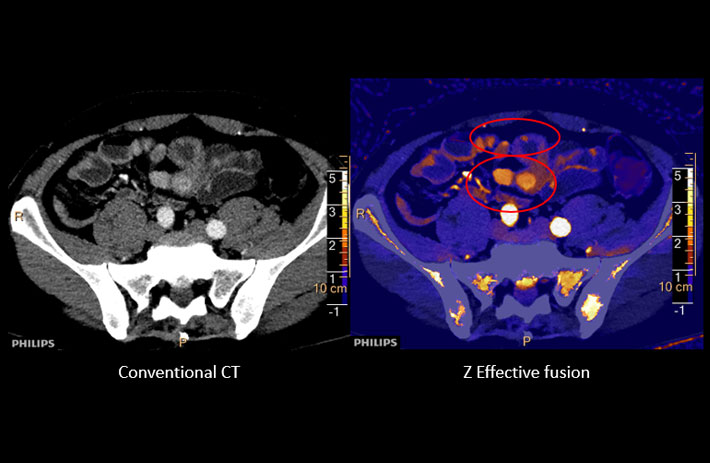

Mit dem Spektral-Detektor-CT werden Spektraldaten automatisch bei jedem Scan erfasst. Die Informationen stehen jederzeit auf der Scankonsole, der CT-Workstation sowie an jedem PACS-Arbeitsplatz zur Verfügung, sodass es nicht notwendig ist, den Patienten erneut zu scannen, bspw. wenn initial zufällige Anomalien festgestellt wurden. Dadurch profitieren Anwender durch eine höhere Diagnosesicherheit und weniger Nachuntersuchungen auf anderen bildgebenden Systemen. Unsere Fallsammlung zeigt, welchen klinischen Mehrwert der Spektral-Detektor-CT in unterschiedlichsten Anwendungsbereichen in der klinischen Routine bringt. Jede Woche gehen neue Fälle live.